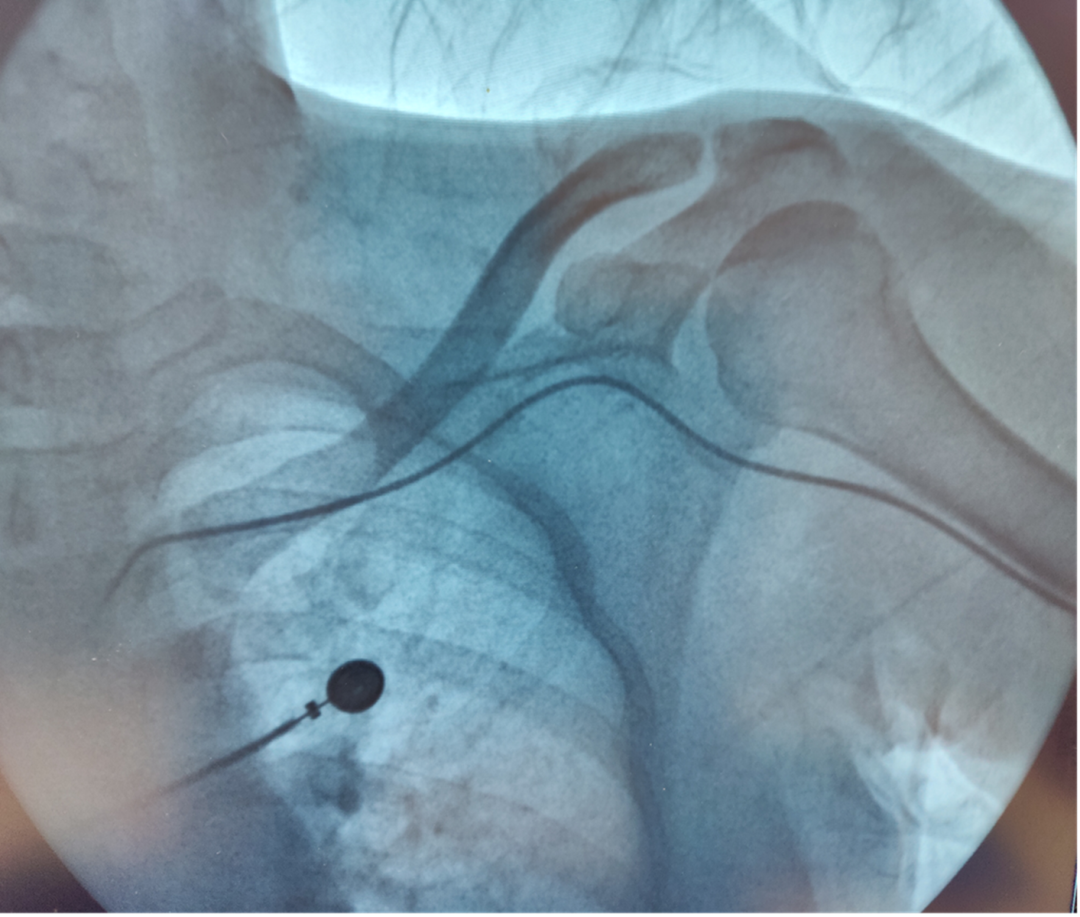

病例分享 | 云县人民医院胸血管外科治疗一例内瘘术后左上肢静脉血栓闭塞